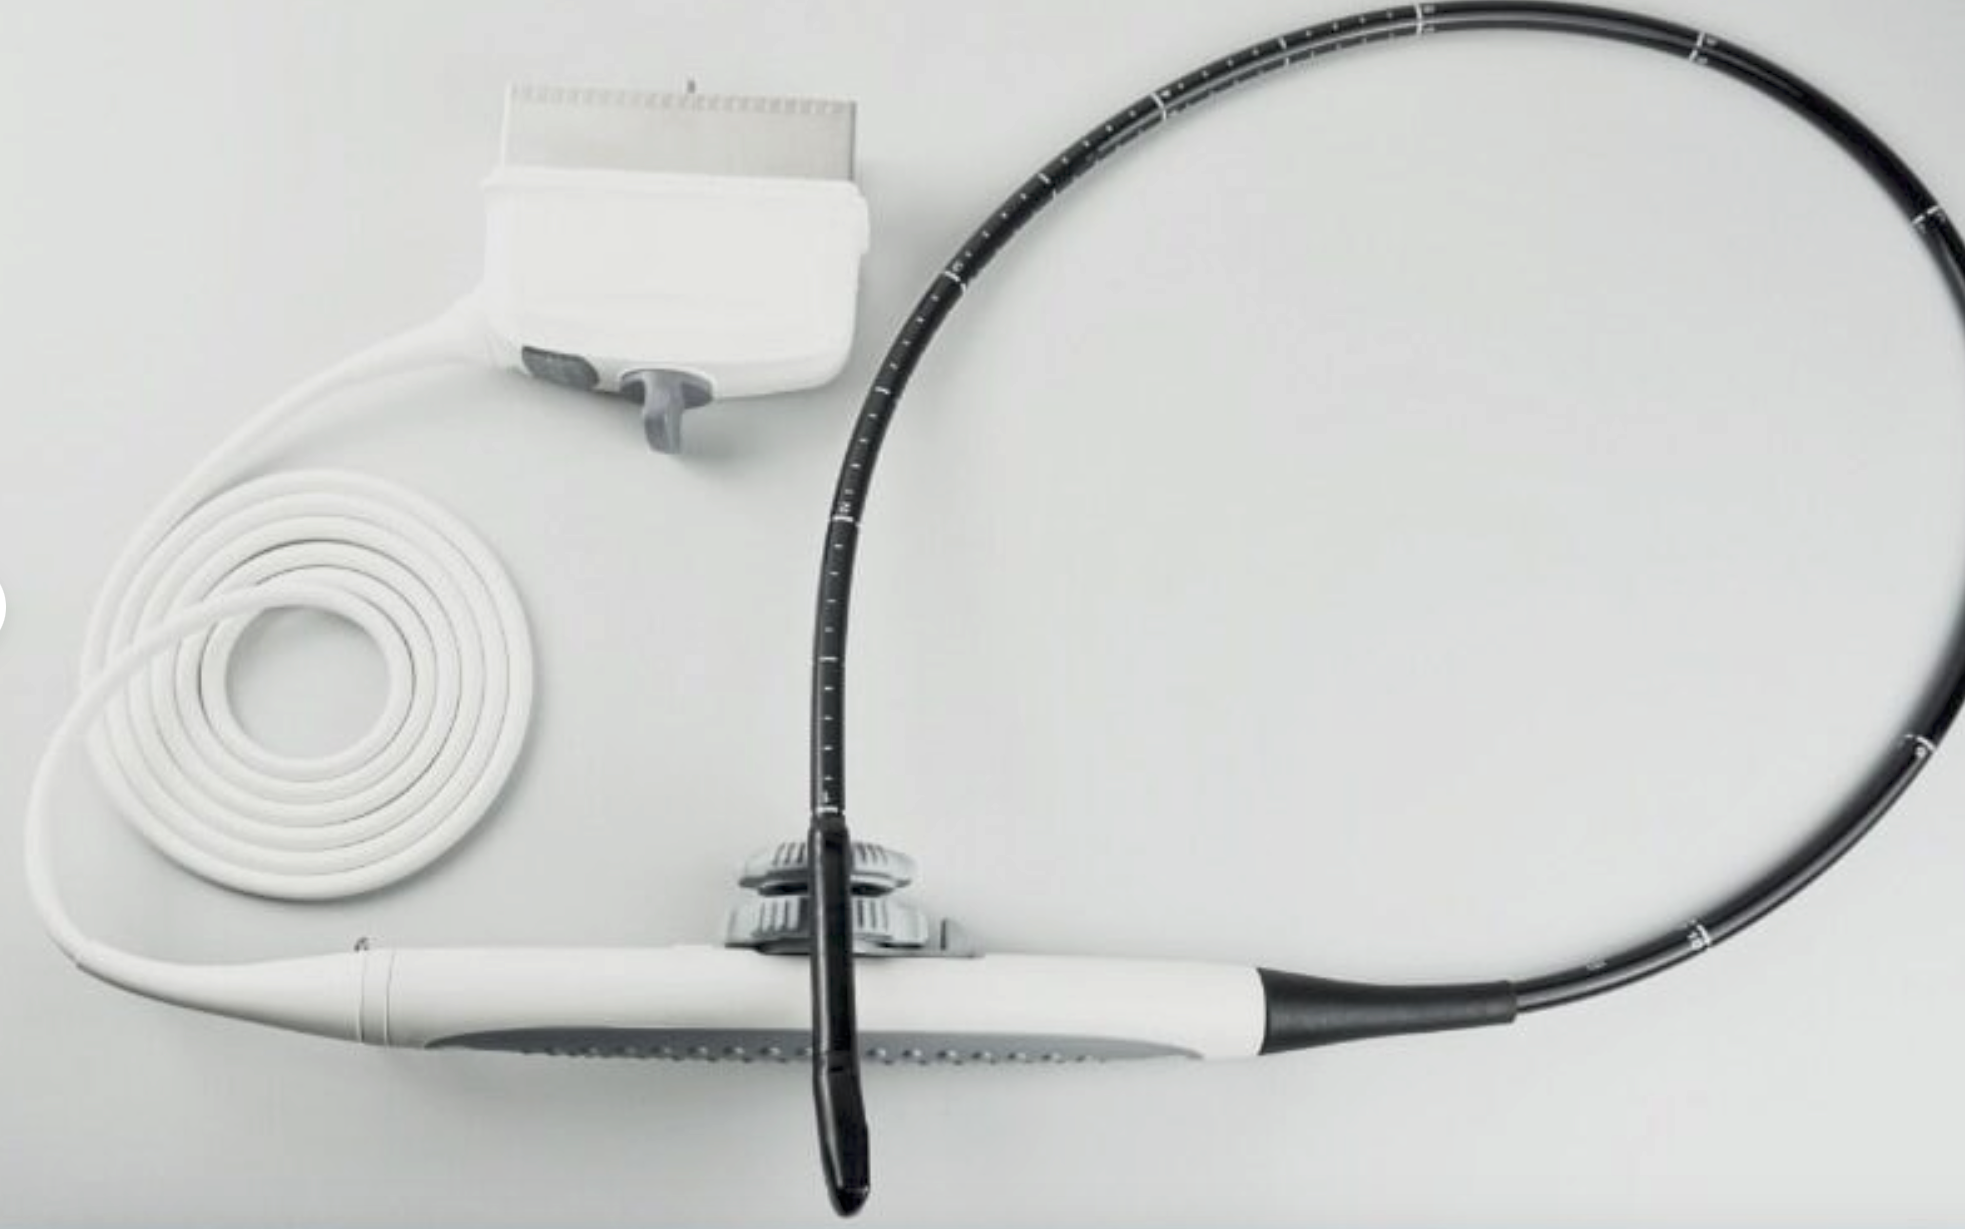

Connectors: 2 probe connectors

software: NEW External 3D Software